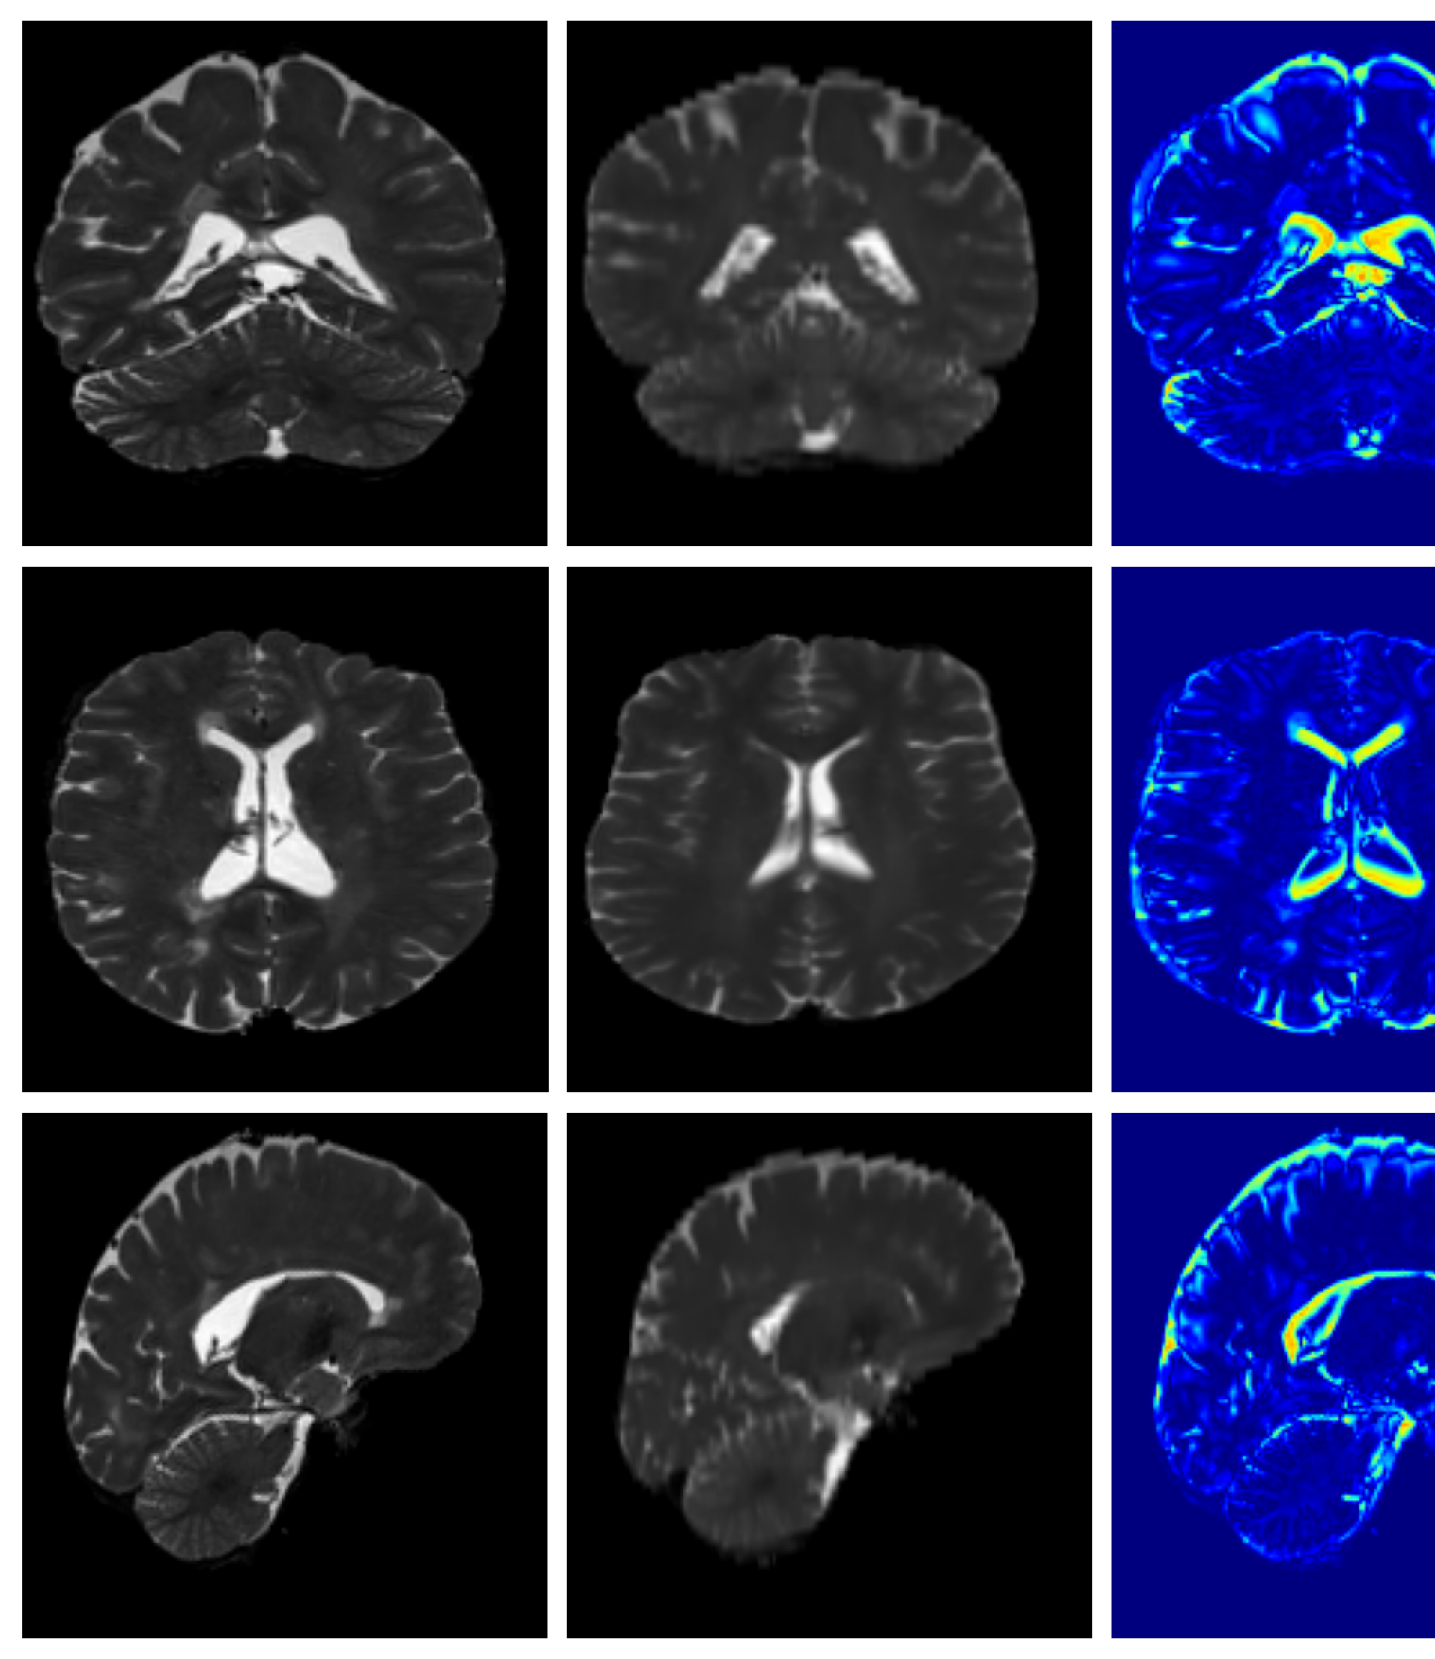

Qualitative T1w results are shown in Figure 2, with further examples for other modalities in Appendix A.8. LoHiResGAN and Res-SRDiff produce unrealistic images with severe artifacts, likely arising from bias fields, sharp intensity artifacts, and other noise not present during training. UniRes generates oversmoothed images, likely due to its TV prior and its reliance on information from multiple input modalities, whereas we apply it unimodally. Di-Fusion shows less pronounced but still notably blurry, voxelated reconstructions which lack the fine-grained details generate by our method. This is likely, in part, due to our use of synthetic rather than real noisy training data, which the method was designed for. As such data is scarce, and in our case unavailable, this requirement represents a significant limitation of Di-Fusion. SynthSR, whilst not as well as our method, does preserve key anatomical structures. However, our difference maps show reduced contrast, further supporting the strong quantitative results shown in Table 2.

For both the Clinical and Low-field datasets, low-resolution images are skull-stripped and normalized to [-1, 1]. The alignment to MNI space is required by forward model given in Equation 11 and is achieved by recomputing the affine transformation through centroid alignment of anatomical labels from SynthSeg Billot2023 segmentations with the corresponding atlas centroids. Example low-resolution images are shown in Figure 6.

A.8 Additional qualitative restoration results

Additional qualitative results for the Clinical dataset are given in Figures 7, 8 and 9, and for the Low-field dataset in Figures 10 and 11.